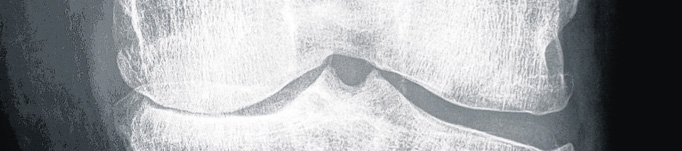

• Degenerative Veränderungen großer und kleiner Gelenke (mit Ausnahme der Hüftgelenke) z. B. des Kniegelenks bei einer Gonarthrose (siehe Abbildung)